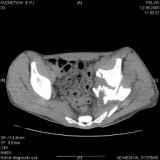

Уважаемые коллеги! Хотелось бы услышать совет по тактике лечения представлленого больного.Поступил после лечения в одном изотделений области. Травма 2,5 месяца назад. После выведенияиз шока был произведен остеосинтез перелома бедра, предплечья, до перевода к нам проводилосьвытяжение по оси шейки бедра за стержень, введенный в большой вертел. На сегодня деформацияригидна, клинически мобильности не определяется. Заранее признателен. P.S. Данный вид травм не включен в перечень "высокотехнологичных операций", направить длялечения по квотам Минздрава очень сложно.

Привет, Леонид. Оскольчатый высокий двухколонный перелом в такие сроки трогать не надо, т.к. это про такие переломы сказано: "кто с ножом на Ж. пойдет тот в ней и останется...".